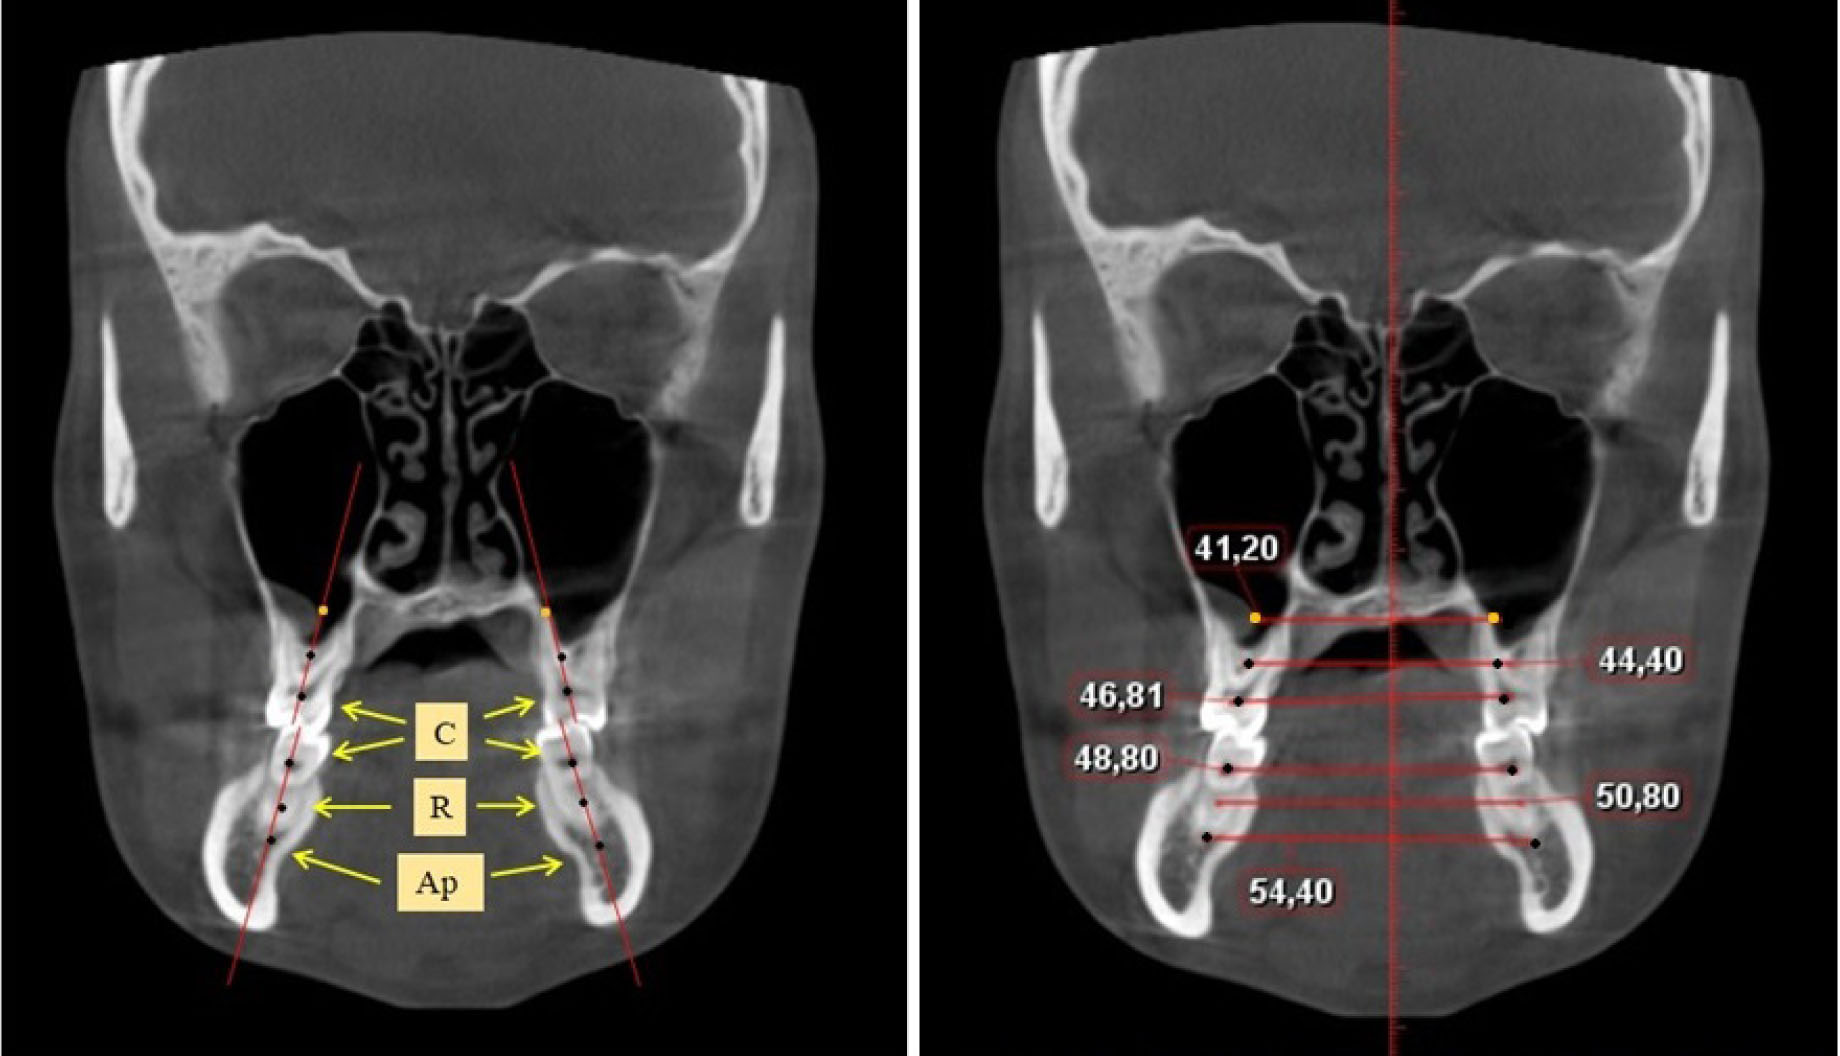

Определение ширины задних отделов зубочелюстных дуг проводили на срезах КЛКТ через дистальные поверхности вторых моляров. Проводили условные срединные вертикали вторых моляров, на которых устанавливали точки на уровне шеек зубов («С»), на уровне середины корня («R») и на уровне апикальной части корня («Ар»), как на верхней, так и нижней челюсти (рис. 2).

Рис. 2. Определение ориентиров и измерение ширины зубочелюстных дуг на КЛКТ в коронарной проекции

Рассчитывали коэффициент соотношения ширины лица с размерами альвеолярных дуг между цервикальными точками вторых верхних моляров (фациально-цервикальный коэффициент).

Ширина альвеолярных дуг на КЛКТ на уровне шеек дистальной стороны вторых моляров на верхней челюсти была в среднем по группе (53,12 ± 1,14) мм. Таким образом, в целом по группе, фациально-цервикальный коэффициент составил (2,66 ± 0,02), что позволяло данную величину использовать как эталон ширины заднего отдела арок. Ширина альвеолярных дуг на КЛКТ на уровне шеек дистальной стороны вторых моляров на нижней челюсти была (54,16 ± 1,23) мм. Превышение размера в (1,02 ± 0,01) раза может быть использовано в качестве расчетного показателя для определения оптимальной ширины альвеолярного гребня нижней челюсти без атрофии ее альвеолярной части.

Ширина альвеолярных дуг на уровне середины корня вторых моляров верхней челюсти была в среднем по группе (50,11 ± 0,83) мм. Таким образом, различия в размерах в меньшую сторону составили (3,01 ± 0,03) мм. Таким образом, различия в размерах между расчетной и фактической в пределах 3 мм была характерны для атрофии альвеолярного отростка до уровня середины корня, что можно определять как атрофию 2-й степени.

Ширина альвеолярных дуг на уровне середины корня вторых моляров нижней челюсти была в среднем по группе (57,44 ± 1,37) мм. Таким образом, различия в размерах в большую сторону составили (3,26 ± 0,05) мм. Таким образом, различие в размерах между расчетной и фактической в пределах 3 мм было характерно для атрофии альвеолярной части до уровня середины корня, что можно определять как атрофию 2-й степени.

Ширина альвеолярных дуг на уровне апикальной части корня вторых моляров верхней челюсти была в среднем по группе (47,02 ± 0,93) мм. Различия в размерах (по сравнению с расчетной величиной) в меньшую сторону составили (6,1 ± 0,07) мм. Таким образом, разница в размерах между расчетной и фактической величиной более 6 мм была характерна для полной атрофии альвеолярного отростка до уровня середины корня, что можно определять как атрофию 3-й степени.

Ширина альвеолярных дуг на уровне апикальной части корня вторых моляров нижней челюсти была в среднем по группе (60,14 ± 1,22) мм. Различия в размерах (по сравнению с расчетной величиной) в меньшую сторону составили (5,96 ± 1,07) мм. Таким образом, разница в размерах между расчетной и фактической величиной более 6 мм была характерна для полной атрофии альвеолярного отростка до уровня середины корня, что можно определять как атрофию 3-й степени.